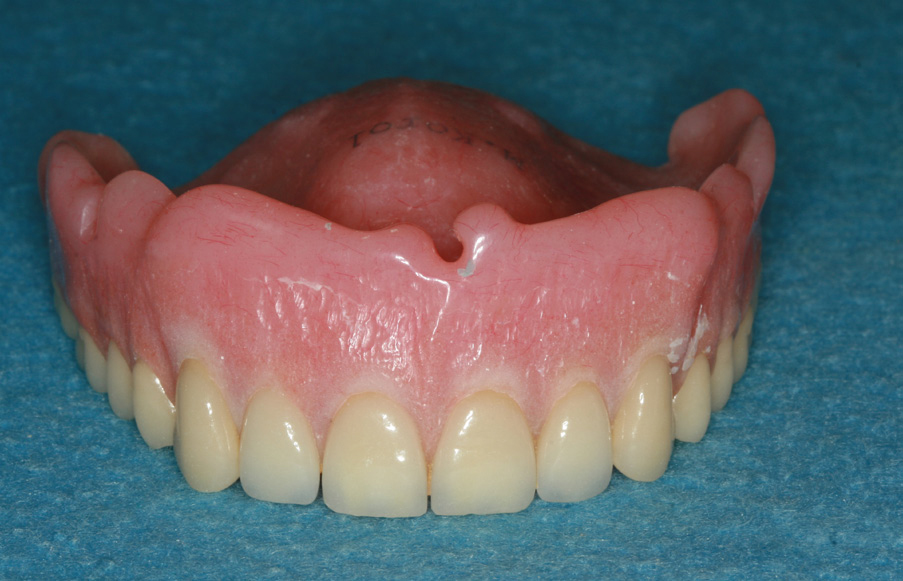

Because the maxillary arch is wider than the mandibular arch, and the cancellous bone is more porous, four to six implants are utilized for a maxillary overdenture. An advantage of having an implant-supported overdenture in the maxilla is that the palatal area remains uncovered to the soft palate. Having the palate open to the taste buds allows for an enhanced sense of taste. Another advantage is relief from triggering the gag reflex. A properly inserted overdenture can be inserted without adhesives and easily removed, allowing for consistent and thorough cleaning. Finally, it produces better lip support for patients who have experienced bone loss in the anterior area.

Correctly completing a treatment plan for the edentulous patient is very important. Some edentulous patients may not be candidates for fixed overdentures due to the lack of existing alveolar bone. To restore the lip support, a flange is often necessary, or an extensive amount of bone grafting must be completed. A flange cannot be attached onto a fixed bridge because the patient will not be able to clean under it (Figure 24).

Figure 24 – Overdenture with flange to restore lip support

Figure 24